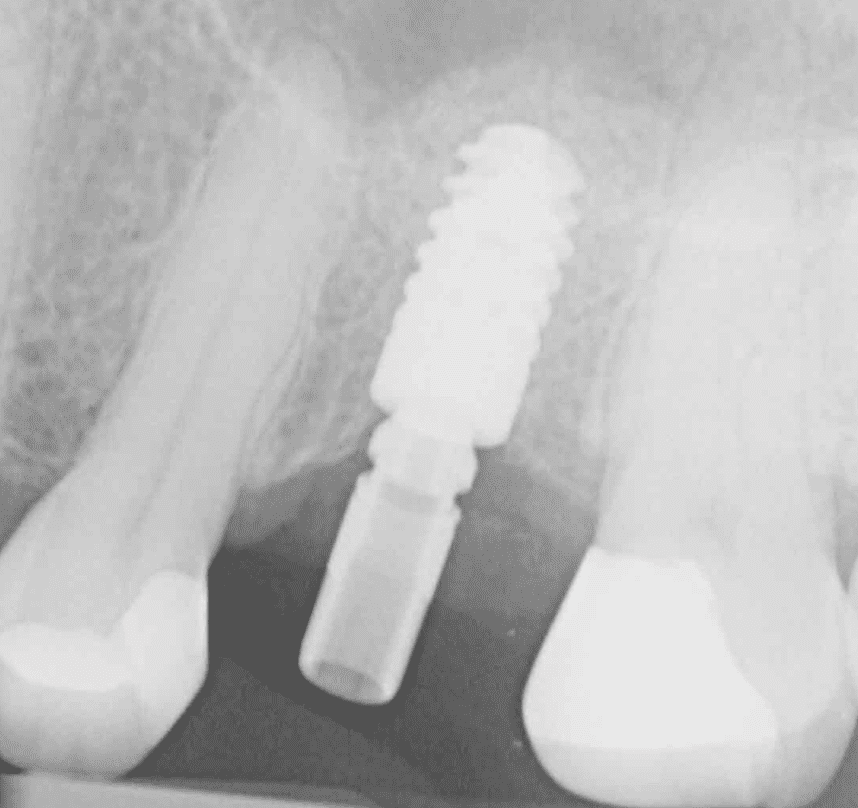

Jonny Jaffa

BDS DipImpDent RCS (Eng)